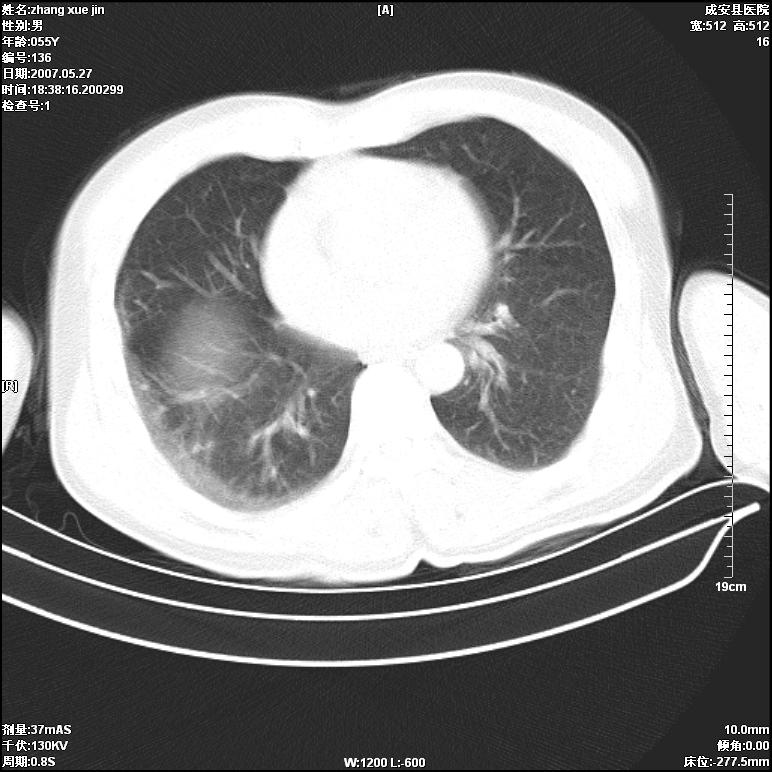

病人 男 53岁 从高处摔伤 行胸部ct检查,纵隔窗没事未上传,肺窗示,右侧胸膜下见条状稍高密度影,是胸膜下线还是右下肺轻度挫伤?意见不一,请分析。

右肺下叶胸膜下弧形窄带状模糊影,结合病史,考虑肺挫伤。

应该把位置摆正,用吸气相或呼气相分别扫描,如果在深吸气相上无此影,支持正常肺坠积差。如果有那就是肺挫伤。

倾向前者:正常肺坠积差

体位不正,左侧纵隔旁胸膜下亦见条带状略高密度影,考虑为坠积效应所致。

正常肺坠积差

正常肺坠积差可能性大,